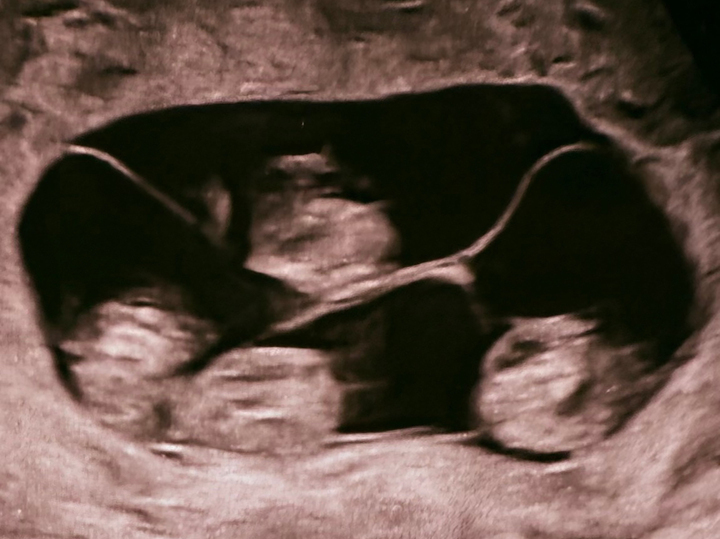

В Санкт-Петербурге зафиксирован редкий случай в акушерской практике: 47-летняя женщина родила четверняшек. Беременность была однояйцевая, поэтому малыши выглядят очень схоже и являются практически «копиями» друг друга. О том, как проходили роды и какие сложности преодолели врачи и мать, читайте в новом материале Пятого канала, который публикуют «Известия». В Санкт-Петербурге в родильном доме №17 у 47-летней женщины родились четыре девочки при однояйцевой беременности. По данным врачей, речь идет о крайне редком случае монохориальной четверни, когда все дети развиваются в одной плаценте и имеют идентичный генетический набор. Специалисты отмечают, что подобные роды практически не встречаются в медицинской практике: по мировой статистике, вероятность составляет один случай на 15,5 миллиона беременностей. В России такие случаи ранее не фиксировались. Роды проходили с помощью кесарева сечения на 32-й неделе беременности. Решение о досрочном родоразрешении медики приняли из-за повышенных рис

В Санкт-Петербурге в родильном доме №17 у 47-летней женщины родились четыре девочки при однояйцевой беременности.

По данным врачей, речь идет о крайне редком случае монохориальной четверни, когда все дети развиваются в одной плаценте и имеют идентичный генетический набор.

Специалисты отмечают, что подобные роды практически не встречаются в медицинской практике: по мировой статистике, вероятность составляет один случай на 15,5 миллиона беременностей. В России такие случаи ранее не фиксировались.